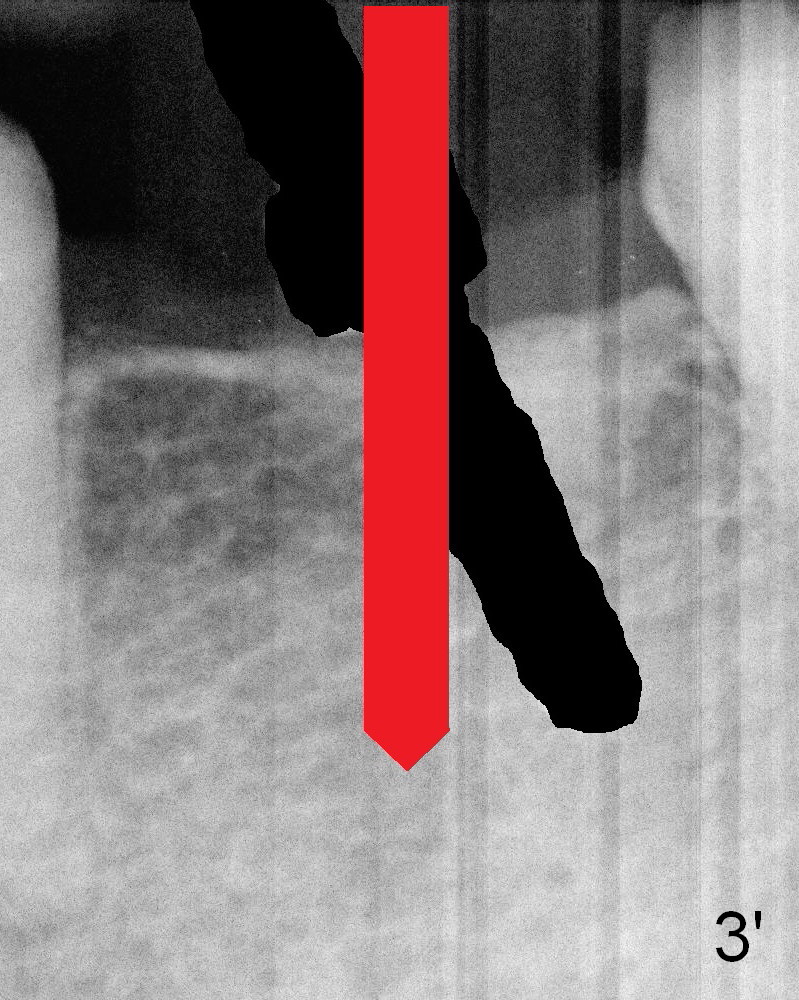

The bone is felt soft during initial osteotomy (Fig.3).   More importantly the parallel pin is not perpendi-cular to the crest.  Ideally after withdrawal of the pin (Fig.3' black area), the trajectory of the osteotomy Should have been corrected so that the drill is perpendi-cular to the crest (red arrow).